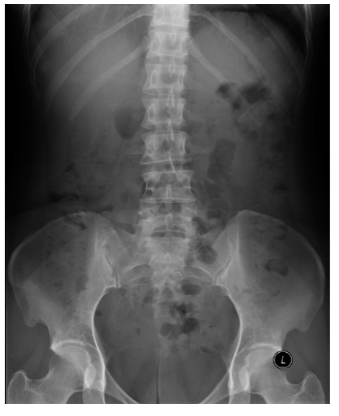

What is depicted in this AXR? [1] What does this indicate? [1]

**Abdominal aortic aneurysm - AAA** There is calcification of the dilated aortic wall Frequently only one side of the aneurysm is visible - as in this image - the other being projected over the spine